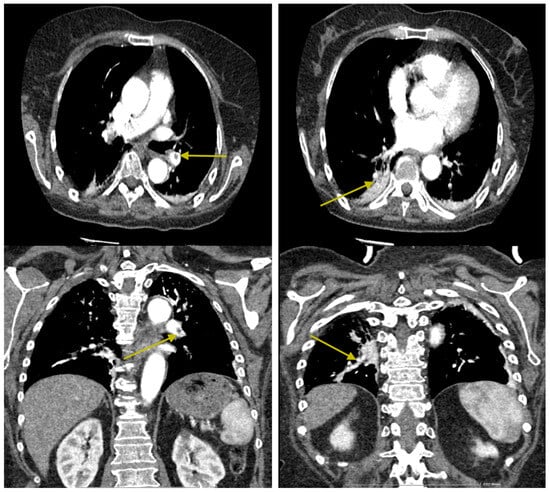

Postoperatively, the patient developed a motor deficit, predominantly affecting the left arm. Her neurological status improved gradually, and she remained conscious, cooperative, and oriented in time and space. Two weeks after the surgical procedure, our patient experienced episodes of dyspnea due to pulmonary thromboembolism in both basal pyramids and the medial segment of the middle lobe (Figure 5). Despite being on postoperative anticoagulation with Clexane 0.6 mL daily, she developed pulmonary thromboembolism, leading to her readmission to the ICU for monitoring, where her Clexane dosage was increased to 0.8 mL twice daily.

Following her readmission to the ICU for pulmonary thromboembolism (PTE), the patient’s condition gradually improved under a meticulous and multidisciplinary monitoring protocol. Daily clinical assessments closely tracked respiratory function, including oxygen saturation and hemodynamic stability, while Doppler ultrasonography was used to rule out further deep vein thrombosis (DVT). CT pulmonary angiographies were performed to monitor thrombus resolution, showing gradual improvement in pulmonary circulation. Adjustments to anticoagulation therapy, including an increased dosage of Clexane to 0.8 mL twice daily, were carefully managed to ensure effective treatment while minimizing bleeding risks. Laboratory markers, such as D-dimer levels, reflected decreasing thrombotic activity over the course of treatment. As her condition stabilized, early mobilization and physiotherapy were introduced, further aiding her recovery. Within days, the patient’s respiratory symptoms resolved, and her neurological status improved significantly. She was fully conscious, cooperative, and oriented, regaining the ability to feed orally and participate in her recovery plan. This steady improvement highlighted the importance of a well-coordinated approach to managing complex postoperative complications.

The patient’s general condition improved under this treatment, and 2 days later, she was transferred back to the ward. Following a cardiology consultation, her anticoagulant therapy was switched to Xarelto 15 mg twice daily (Figure 6).

Figure 5. Intraluminal filling defects are observed in the pulmonary arteries supplying the basal pyramids and the medial segment of the middle lobe, with an appearance suggestive of pulmonary thromboembolism at this level (yellow arrows). Minimal passive subpleural atelectasis is noted bilaterally in the posterior-basal regions. No nodular expansive pulmonary lesions with a tumoral substrate are present. There are emphysematous bullae with a paraseptal apical distribution on the right side. No pleuro-pericardial fluid accumulations are observed. No mediastinal or axillary lymphadenopathy is detected bilaterally. The tracheobronchial tree is within normal limits. Intimal calcifications are present in the thoracic aorta.

Figure 6. Intraluminal filling defects in the pulmonary arteries are significantly reduced in both number and size, with a few small defects persisting in the pulmonary arteries supplying the antero- and mediobasal segments (yellow arrows). Small bilateral posterior-basal atelectases are noted, with a small pseudonodular area in the right basal region showing low iodophilia, which may suggest a small pulmonary infarction. The remainder of the findings are unchanged.